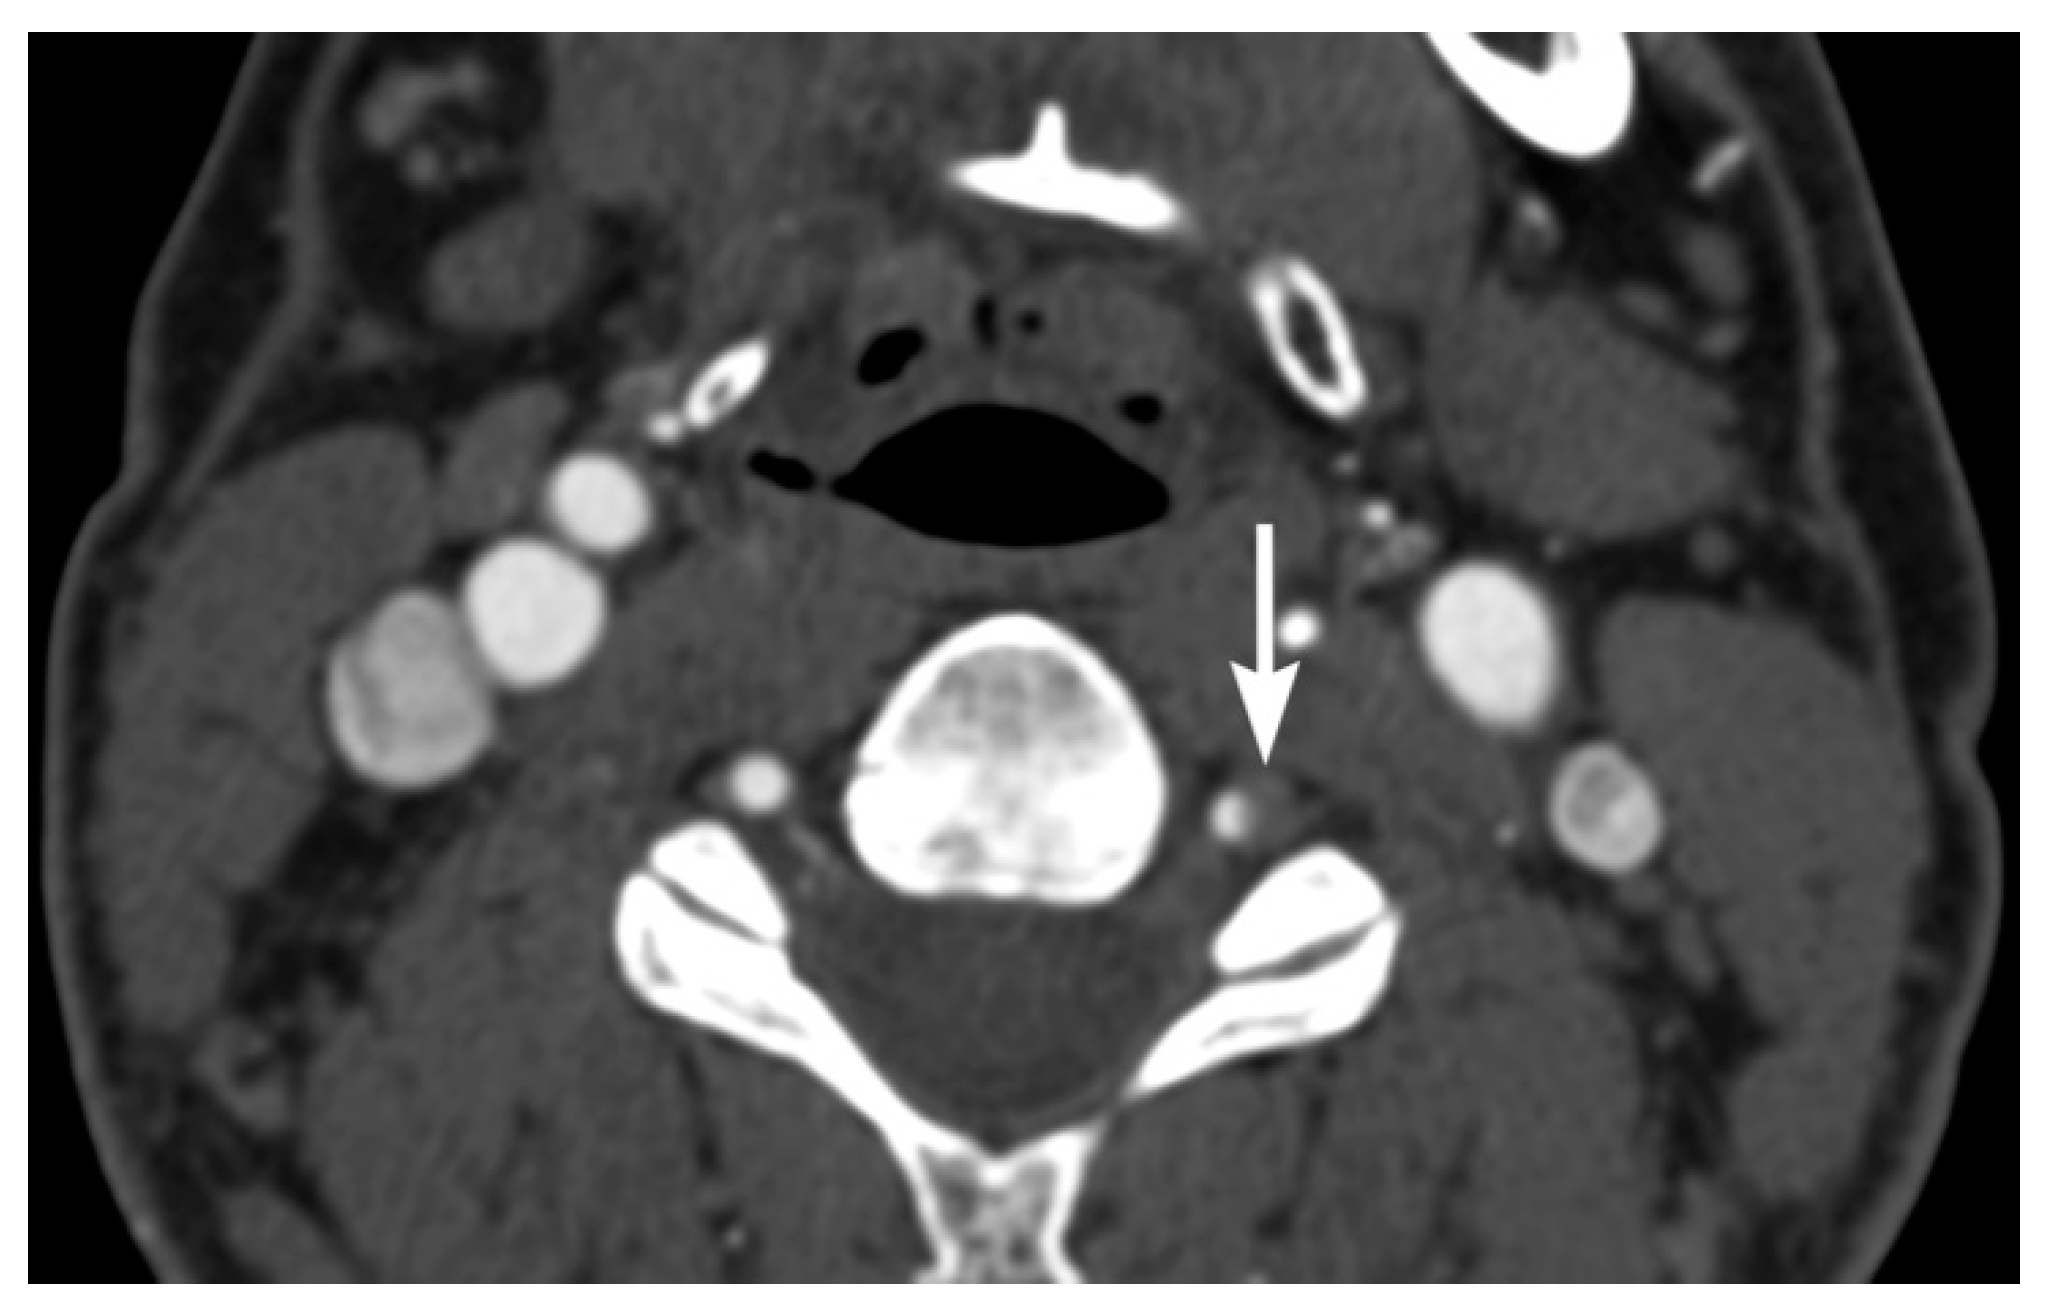

3. Imaging Findings of Arterial Injury